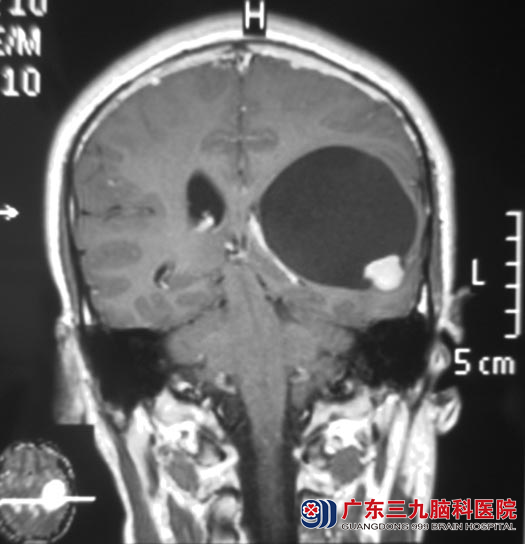

随后,阿丰出现头痛,家里人不放心,劝他去医院做体格检查。头颅CT检查提示:左侧颞顶叶占位性病变,考虑肿瘤性病变。广东三九脑科医院MR检查显示病变大小约6.26cm×5.94cm×5.66cm。

12月9日,由综合神经外科 鲁明主任主刀,在全麻下行左侧颞叶占位性病变切除术,术中导航定位,显微镜下见病变呈囊性,囊壁见淡黄色增生组织,囊腔内可见一实性肿瘤,予全切,经过顺利。病理结果为:低级别节细胞瘤。